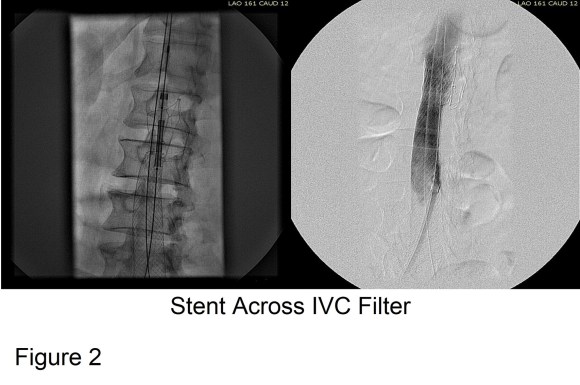

Large WallStents were used to support the recanalized iliocaval system from the common femoral veins to the filter. A Palmaz stent was deployed across the filter (Figure 2).

Figure 3 shows the final result. Interestingly, stents placed across the inguinal ligament into the common femoral vein seem to do fine in contrast to those placed in the artery. IVUS is necessary to confirm good results. Acceptable short term, and durable mid to long term results are reported.